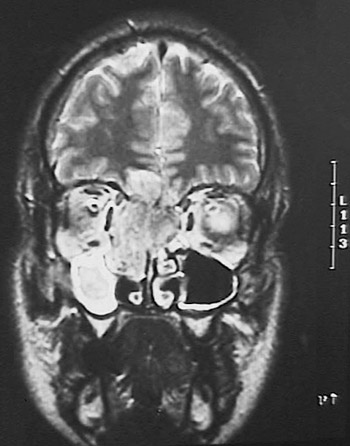

The MRI scan of the head in axial view reveals a mass lesion. This is an olfactory neuroblastoma filling and expanding the nasal cavity and adjacent sinuses on the right. This same mass is seen in coronal view below.